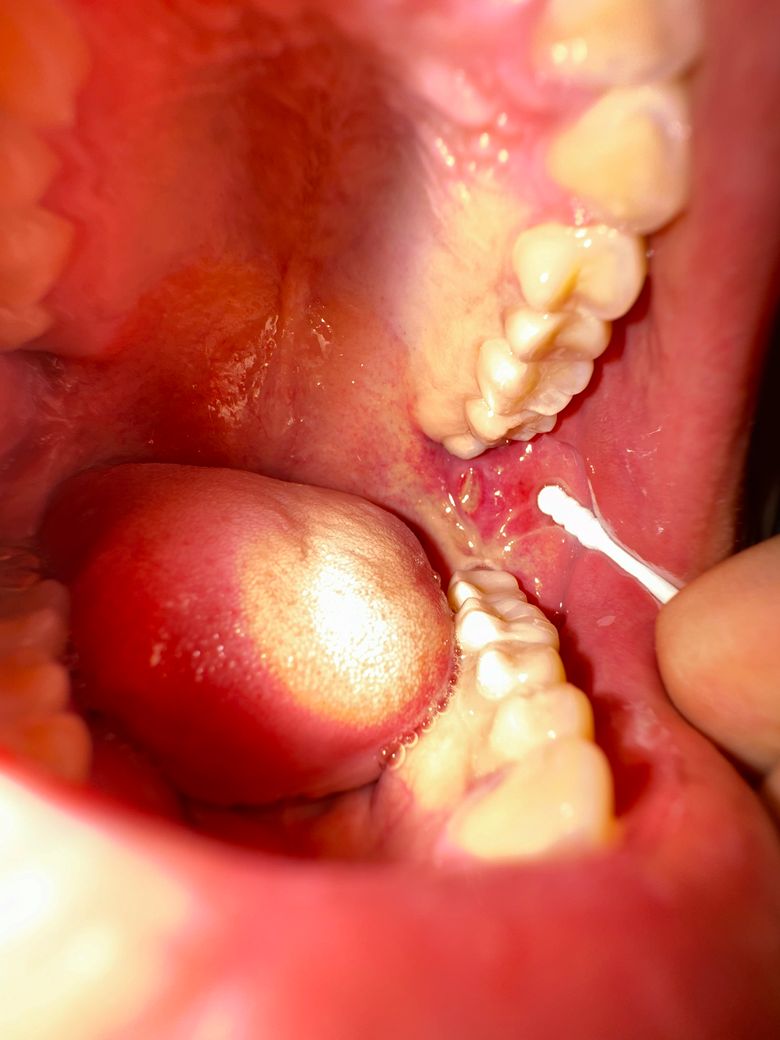

증상은 2,3일 전부터 있었고 왼쪽 턱아래아프고 입이 벌릴려면 아팠고 침삼키면 아픕니다 구내염 맞나요 ?? 병원가봐야한다면 치과가야하나요? 이비인후과 가야하나요??

현재 경험하고 있는 증상인 왼쪽 턱 아래의 통증, 입을 벌릴 때와 침을 삼킬 때의 통증은 구내염 또는 침샘염일 가능성이 있습니다. 구내염은 입 안의 염증으로 인해 통증과 불편함을 유발할 수 있으며, 침샘염은 침샘에 염증이 생겨 통증과 부기를 유발할 수 있습니다. 구내염의 경우 일반적으로 입 안에 통증이 있는 궤양이나 염증이 보이는 반면, 침샘염은 보통 턱 아래의 부기와 통증이 동반될 수 있습니다.

본인도 모르게 치아에 점막이 상처 입어 생긴 구내염의 가능성이 생각됩니다. 치과 진찰을 받아보시기 바랍니다.